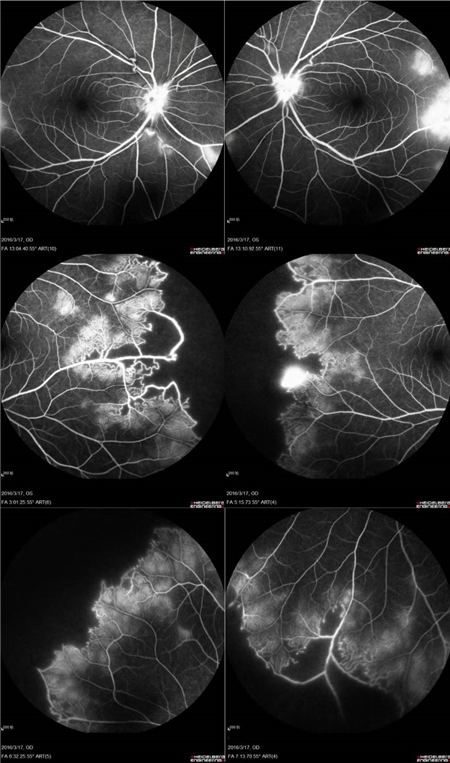

特发性视网膜血管炎、动脉瘤和视神经视网膜炎综合征(Idiopathic Retinal Vasculitis, Aneurysm, and Neuroretinitis syndrome,简称IRVAN综合征)是一种病因不明的较为少见的视网膜血管炎性疾病,此病症常在30-40岁发病且多为女性发病。在发病的前期,如果进行及时有效的治疗干预,预后效果多数较好。但一拖再拖,错过最好的治疗时间,可引起严重的并发症。在这里提醒大家,一定要密切关注自己眼部突发情况的出现,警惕眼前突然发生黑影飘动,视力下降的情况,尽早就医。

视盘附近的动脉和动脉分叉处出现瘤样动脉扩张,视盘充血,边界不清,引起视盘周围视网膜内硬性渗出;视盘周可有少量放射状出血。

静脉不规则扩张和血管鞘膜,周边部小血管广泛闭塞,交界处毛细血管扩张和异常吻合。

严重者可发生从周边到黄斑的血管闭塞和缺血、玻血、新生血管性青光眼,最终视神经萎缩。